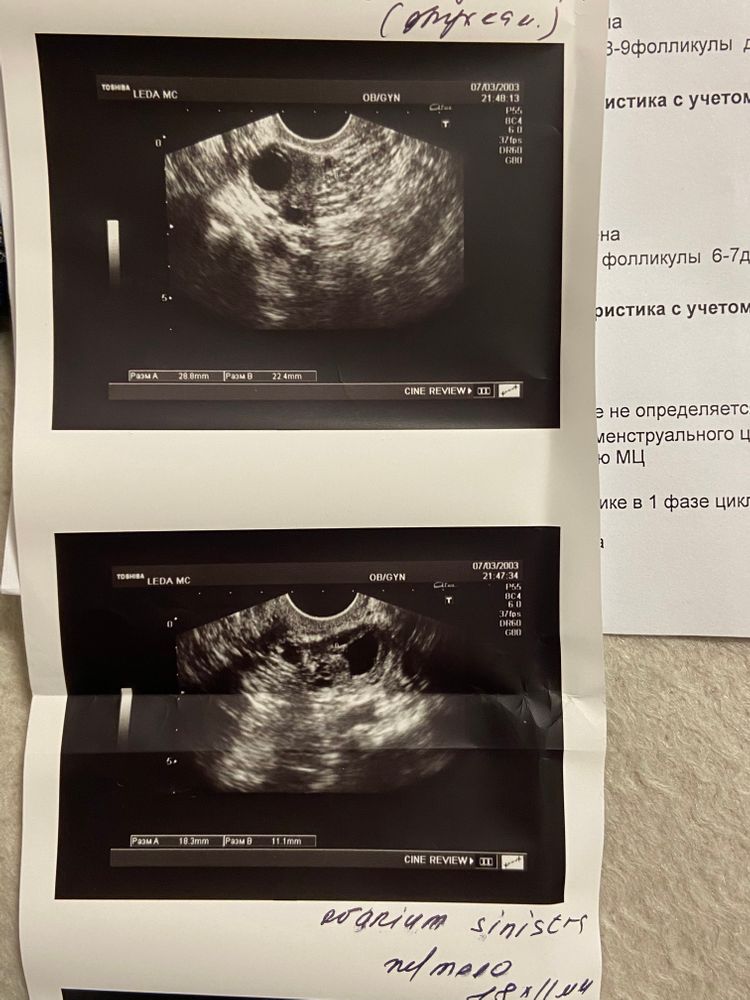

Мира, вот УЗИ. Изображение Изображение

Мария Титова, вроде ЖТ ещё маленькое,наверно не давно была… может 13-14 дц?

У вас с эндометрием проблемы,копайте в эту степь

У вас ранняя о, нужно раньше отслеживать и раньше стараться. Б уже не получится)